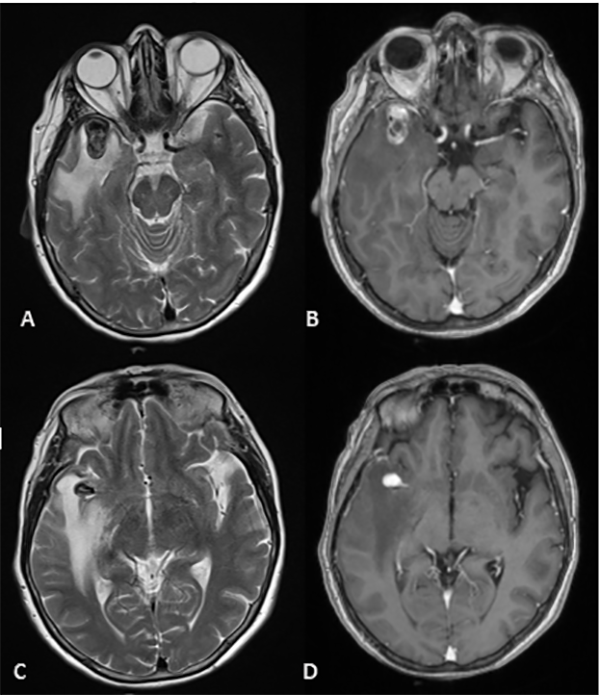

Figura 3:

(RMN) Se observa en corte axial lesión expansiva marcadamente hipointensa en T2 localizada a nivel temporal anterior derecho en relación con el sector distal de la arteria cerebral media homóloga. Tras la inyección de contraste presentó refuerzo heterogéneo, con un componente de aspecto trombosado en el sector basal de la misma, asociado a extenso edema periférico (A, B, C y D).